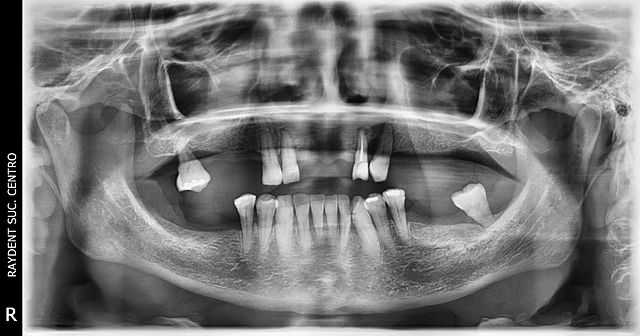

• Radiografía panoramica

Radiografía panoramica

La paciente acudió al laboratorio RayDent para tomarse la radiografía panorámica y de manera general se observo que la perdida ósea horizontal ya es muy avanzada por lo que algunos órganos dentarios ya no tienen sostén adecuado.